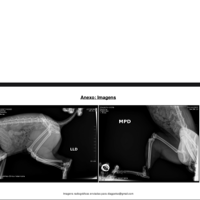

Ela quebrou a patinha traseira esquerda, fraturando dois ossos na junta e ficando com estilhaços de ossos. 😢

O veterinário explicou que ela precisa de uma cirurgia urgente pra tentar salvar a patinha.